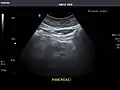

Pancreas: Visualized portions unremarkable.

Pancreas